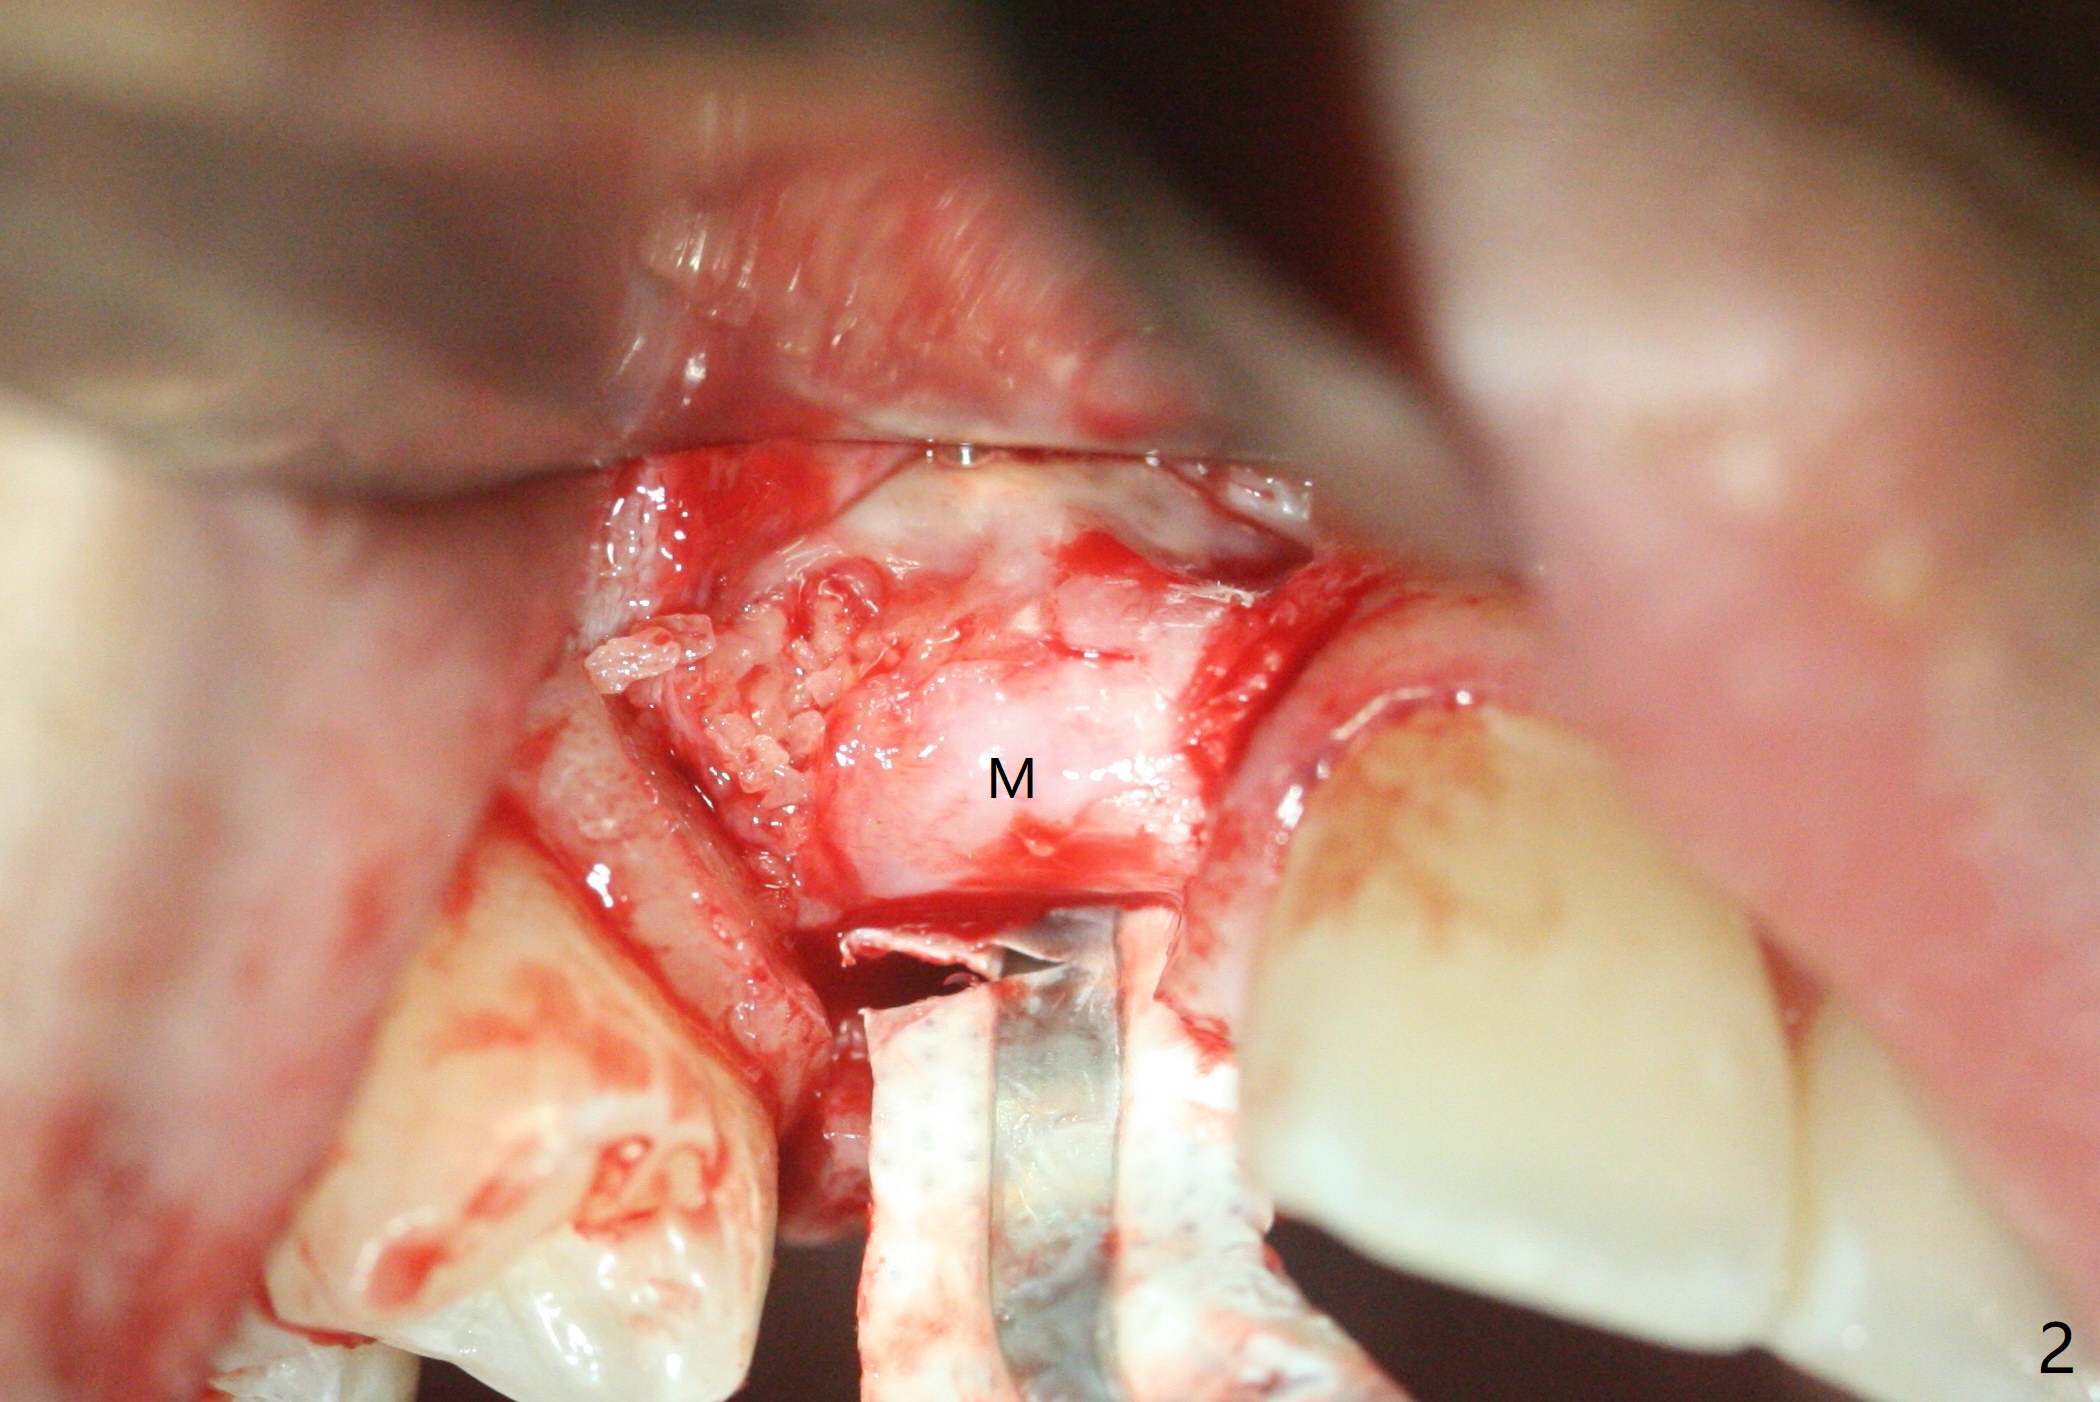

右上尖牙植体拔除,植骨后6个月,切开显示不可吸收膜覆盖的牙槽骨尚饱满(图一),不可吸收膜下面形成一个膜(可能是骨膜,图二:M),在导板指导下,植入3x12(2)毫米一段式植体,颊侧(图三),腭侧(图四)骨下,稍微穿过窦底(图五),植体覆盖粘性骨粉(图六)和PRF膜后,4-0 PGA缝合。伤口有一定张力,使用牙周敷料。术后10天没有疼痛(就没有骨坏死),由于基台存在,牙周敷料没有脱落迹象(图七),也没有撤除。敷料术后13天脱落,伤口好像正常愈合(图八)。由于病人即将回外州上学,提前取模。他喜欢左边牙冠修复形式(牙冠覆盖牙龈),而我们想让牙冠位于牙龈舌侧(图十:T(临时牙冠))。